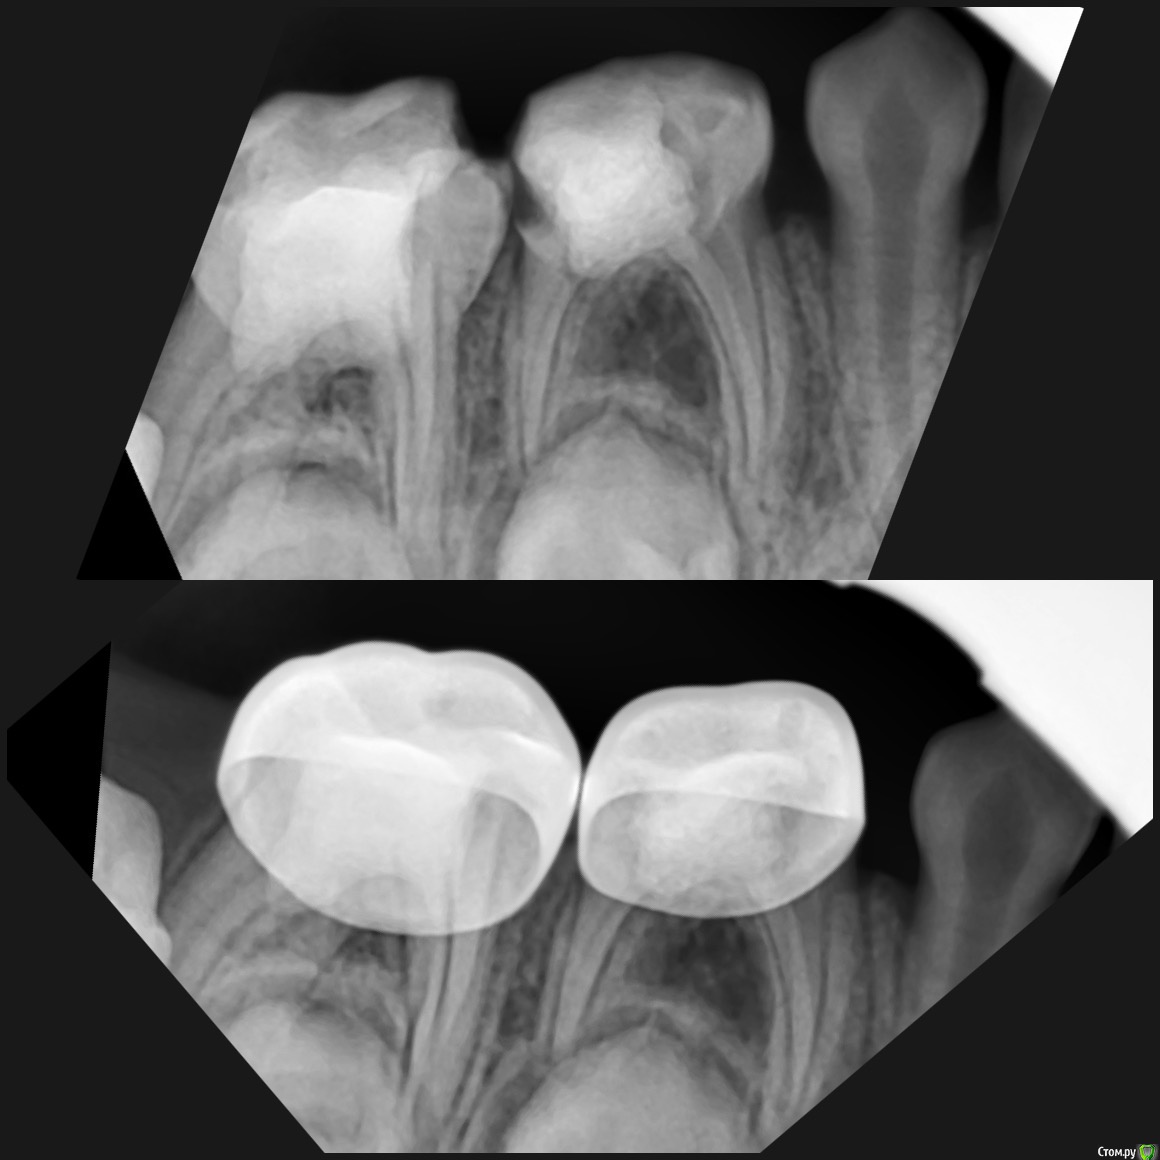

CRAZYDUCK Опубликовано 22 мая, 2018 Автор Поделиться Опубликовано 22 мая, 2018 (изменено) И про короночки ловите. 8.4 и 8.5 ранее ( около двух лет назад ) лечены методом витальной ампутации . Реставрации обширные плюс начался кариес контактных поверхностей . Два года назад я не применяла так широко в практике своей Коронки ( сейчас бы покрыла сразу после ампутации). Изменено 22 мая, 2018 пользователем CRAZYDUCK 1 Ссылка на комментарий

crown Опубликовано 22 мая, 2018 Поделиться Опубликовано 22 мая, 2018 8.4 похоже что есть изменения в бифуркации? Да надо возвращаться к коронкам. Вы где учились их ставить? Ссылка на комментарий

CRAZYDUCK Опубликовано 23 мая, 2018 Автор Поделиться Опубликовано 23 мая, 2018 В нижних 4 часто такая зона, даже в интактных. Я тоже на эту зону всегда недоверчиво смотрю. Я напишу Вам в личку позже где училась . 8.4 похоже что есть изменения в бифуркации? Да надо возвращаться к коронкам. Вы где учились их ставить? Ссылка на комментарий

CRAZYDUCK Опубликовано 24 мая, 2018 Автор Поделиться Опубликовано 24 мая, 2018 В этом клиническом случае хочу обратить внимание коллег на покрытие 8.5 зуба коронкой ( что необычного видите ?). И на использование флосса, чтобы заправить платок дистально за 4.6 . 4.6 начальный кариес , но зуб дистально ещё был прикрыт десной ( фото до лечения не делала без коффердама). Раньше во время работы в эту дистальную зону «трамбовала» Фумку . Следила , чтобы не подтекало . Но !!!!Очень удобно эту десну заправлять флоссом - ничего не течёт 1 Ссылка на комментарий

CRAZYDUCK Опубликовано 24 мая, 2018 Автор Поделиться Опубликовано 24 мая, 2018 8.5 ранее лечен методом витальной ампутации( 1,5 года назад ), но реставрация обширная . Не выдерживает жевательную нагрузку . 2 Ссылка на комментарий